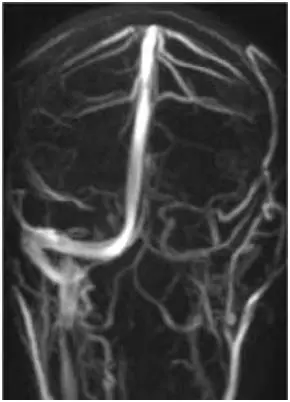

Obiettivi: L’emicrania cronica (CM) è caratterizzata da dolore ricorrente alla testa, spesso associato ad alterazioni elettroencefalografiche (EEG) e ad asimmetrie nella circolazione venosa intracranica. È considerata uno dei sintomi della insufficienza venosa cerebrospinale cronica (CCSVI).

Metodi: Sette pazienti con diagnosi di CCSVI ed emicrania cronica, con o senza altri sintomi, sono stati sottoposti a angioplastica transluminale percutanea (PTA) delle vene giugulari interne. Tutti hanno eseguito risonanza magnetica venografica e/o ecocolordoppler prima della PTA, sette EEG preoperatori e cinque EEG di controllo post-PTA. L’intensità del dolore è stata valutata con una scala numerica prima e dopo l’intervento.

Risultati: Tutti i pazienti hanno mostrato un miglioramento del flusso ematico giugulare dopo PTA. In cinque pazienti su sette è stato osservato un miglioramento del ritmo alfa cerebrale all’EEG post-operatorio e tutti hanno riportato una significativa riduzione del dolore.

Conclusioni: Queste osservazioni preliminari suggeriscono una stretta associazione tra emicrania cronica, anomalie venose intra- ed extracraniche e alterazioni EEG, e indicano la venoplastica come possibile approccio terapeutico da approfondire.